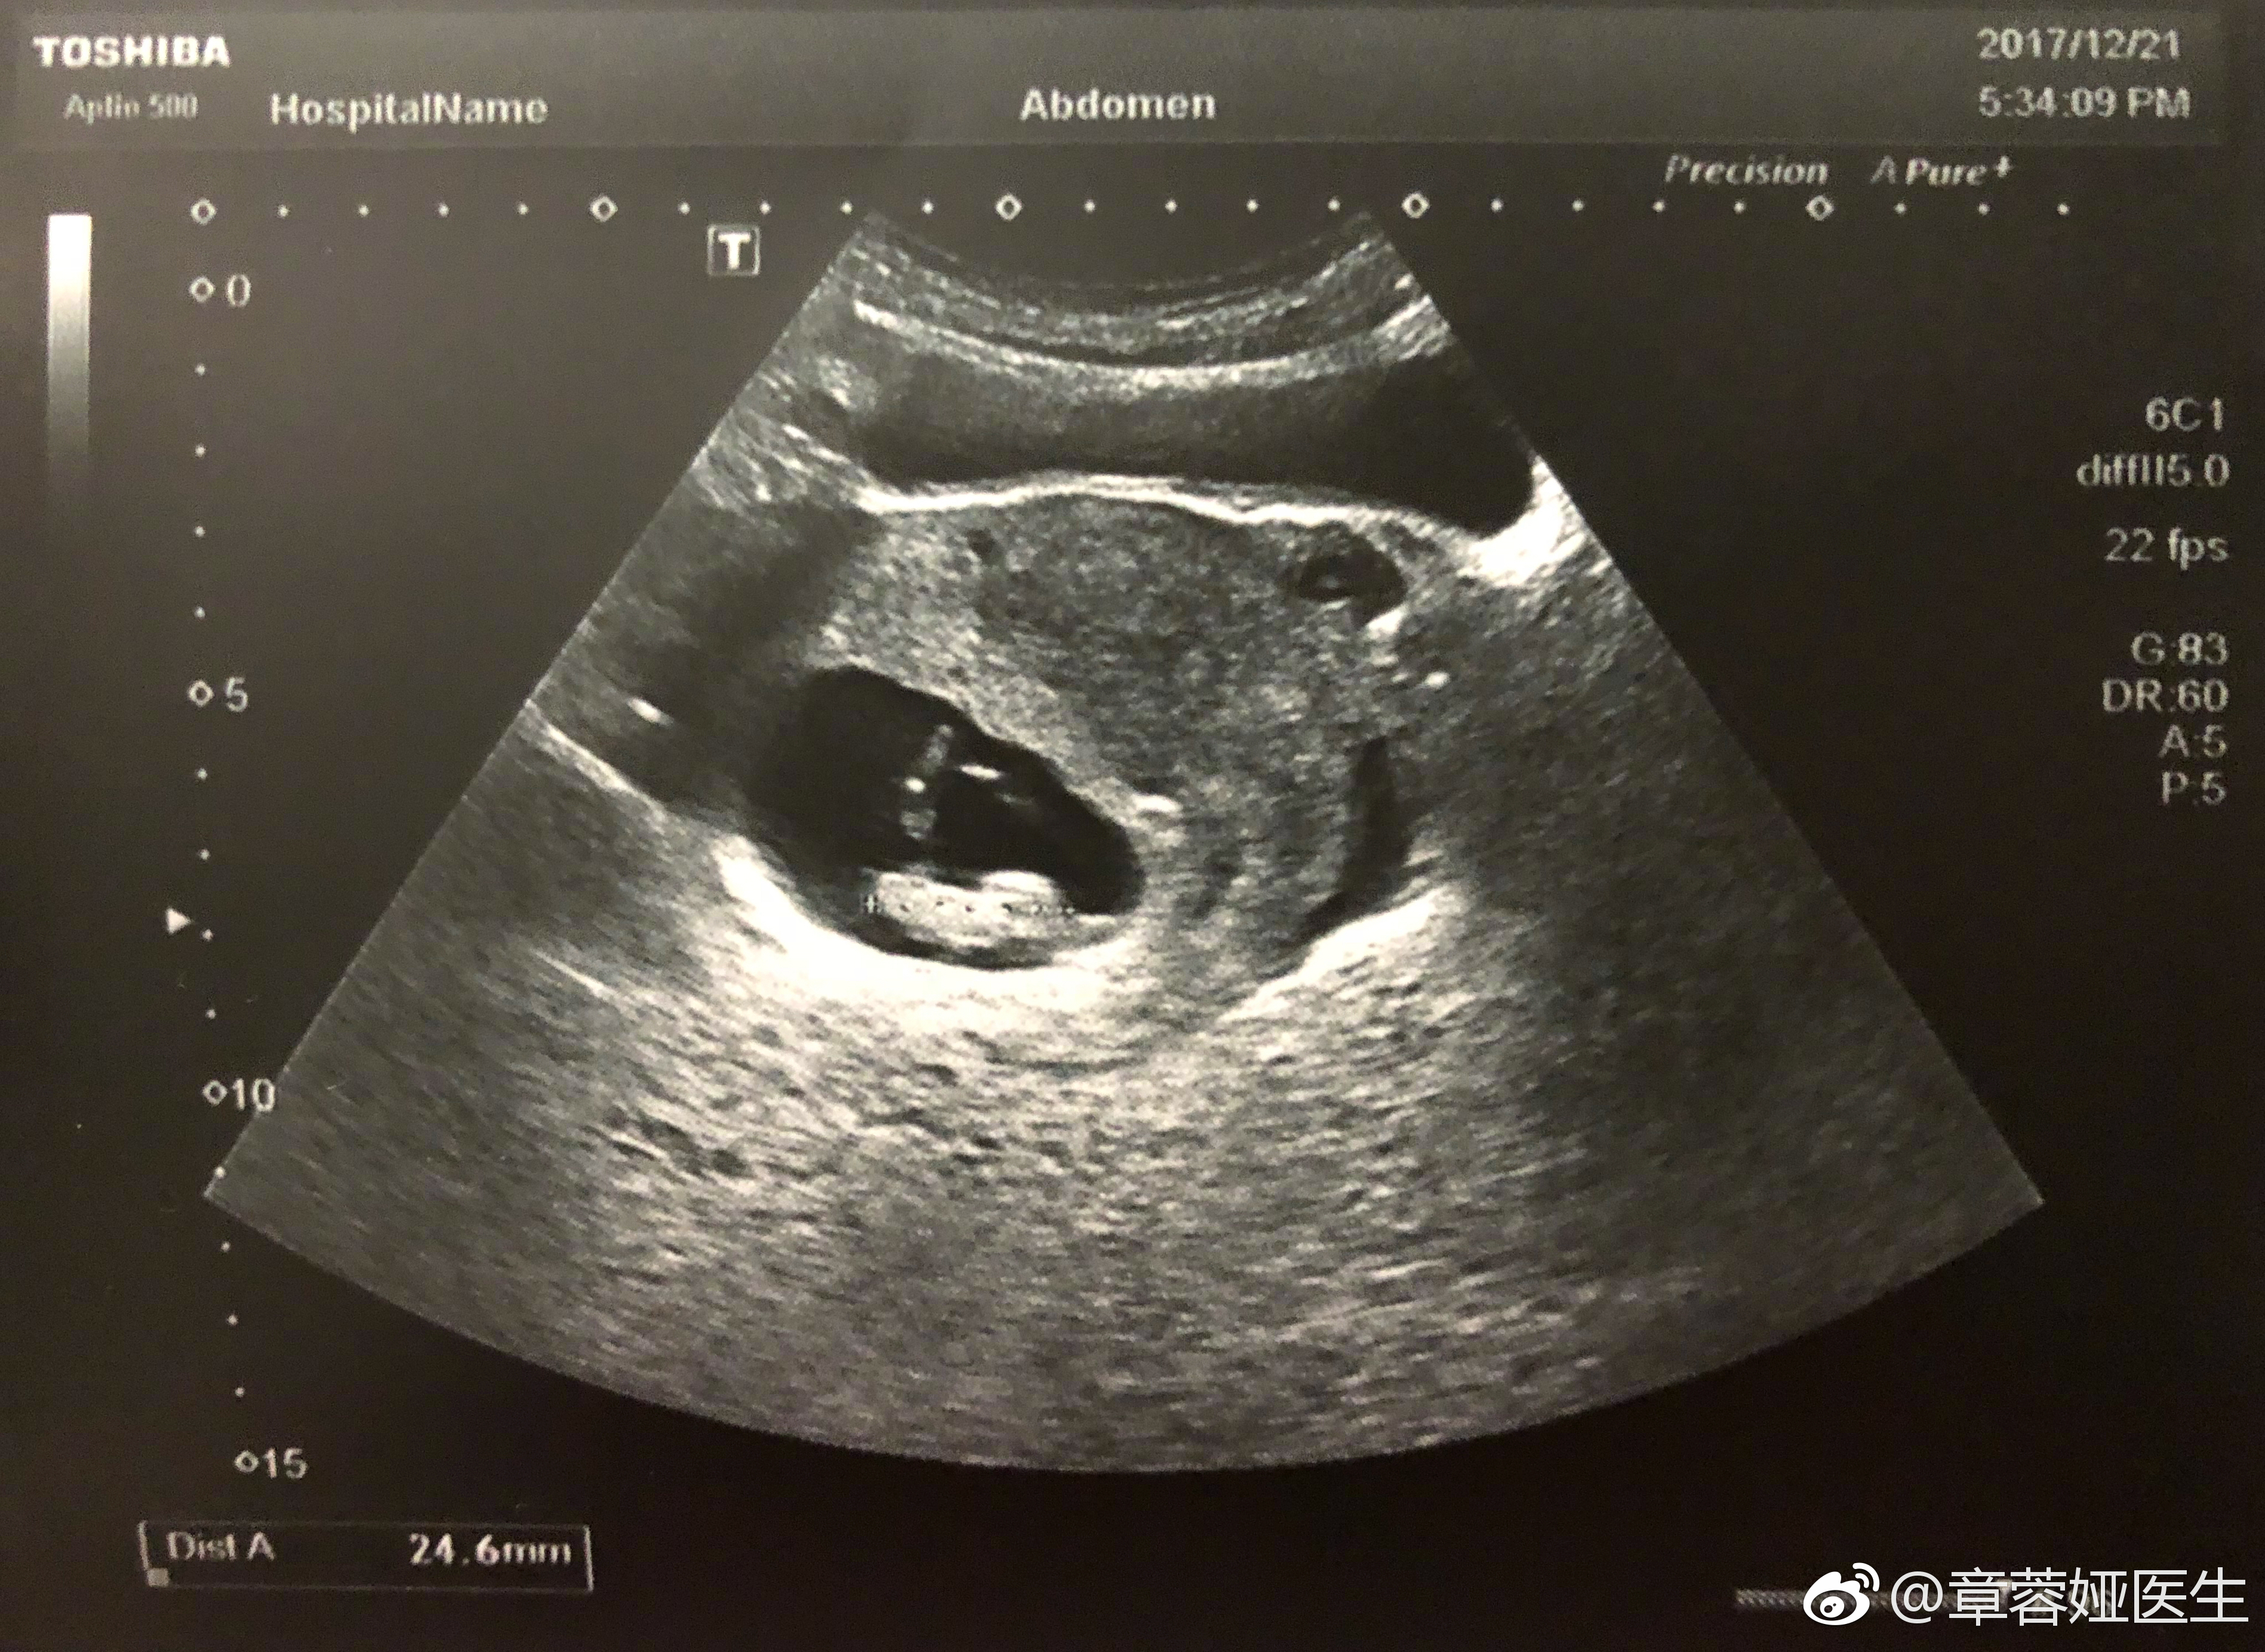

@章蓉娅医生:

我心理素质好,一直扛到孕8周才去做超声。

刚刚做的B超,估得宝宝偏大一周…